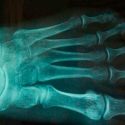

Un grupo de científicos del Instituto Tecnológico de Saltillo (ITS) desarrollaron un material biocerámico celular de baja densidad base sílice para reconstruir o sustituir tejido óseo.

Como resultado de este proceso, los especialistas adquirieron un material bioactivo que induce una respuesta biológica específica en la interfaz debido a la unión entre el tejido y el material, por medio de una capa de hidroxiapatita carbonatada.

Dichos componentes se sometieron a pruebas de bioactividad mediante su hundimiento en un fluido fisiológico simulado de concentraciones iónicas similares al plasma sanguíneo humano, a fin de caracterizar su estructura y morfología.

“Se han hecho pruebas de bioactividad, en las cuales ha respondido satisfactoriamente este material a los estudios fisiológicos, esta es la primera etapa para considerarlo un material bioactivo o un material que pueda utilizarse como prótesis en el cuerpo humano”, indicó la investigadora.